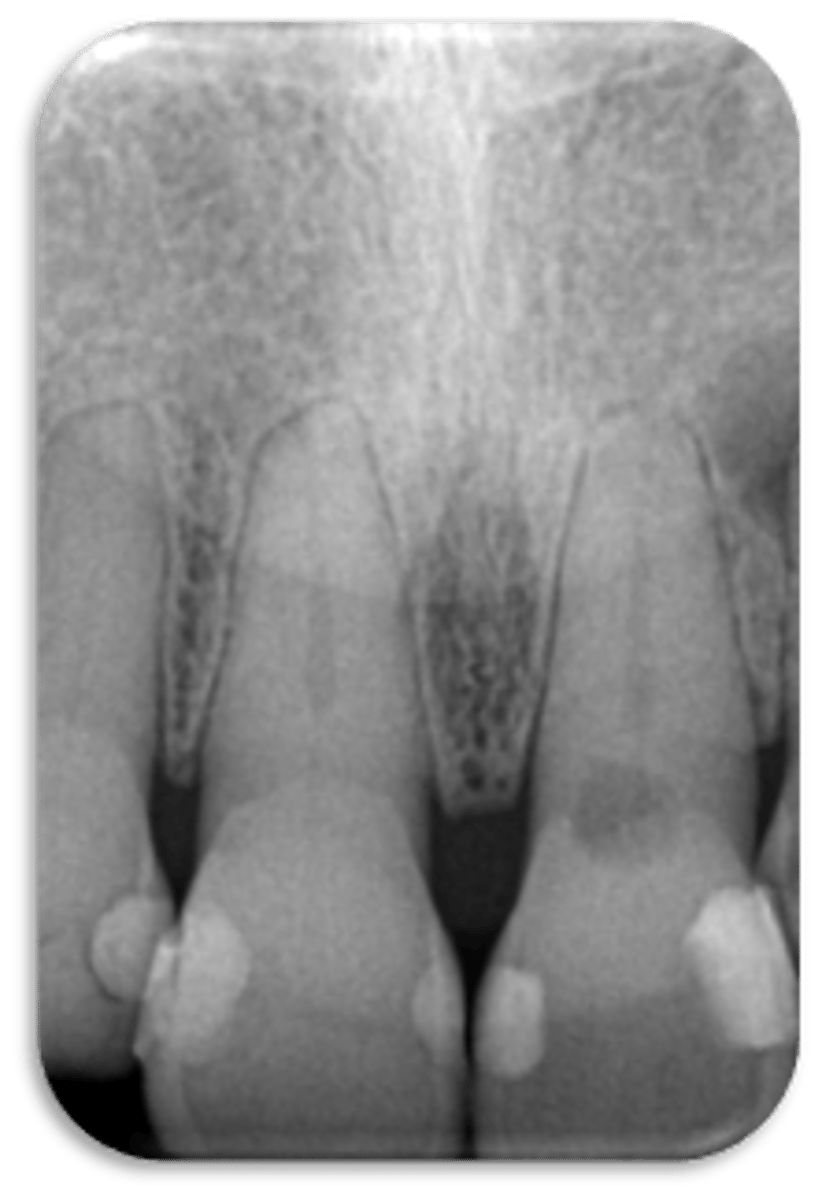

ID the structure:

intermaxillary suture

nasopalatine foramen